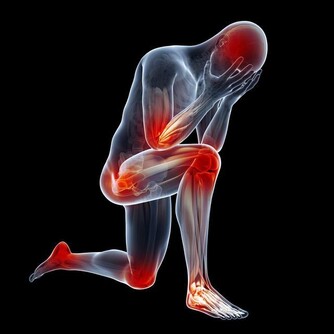

很多人覺得頸椎病是小病,但是如果頸椎病嚴重的話,壓迫到交感神經影響到心臟,可以出現頸源性心髒病,出現心絞痛;壓迫到椎動脈,可能會急轉項時,引發忽然暈倒;壓迫到脊髓,猛地跌倒可能會造成脊髓的損傷,出現肢體癱瘓。這些都是可能的潛在危害。